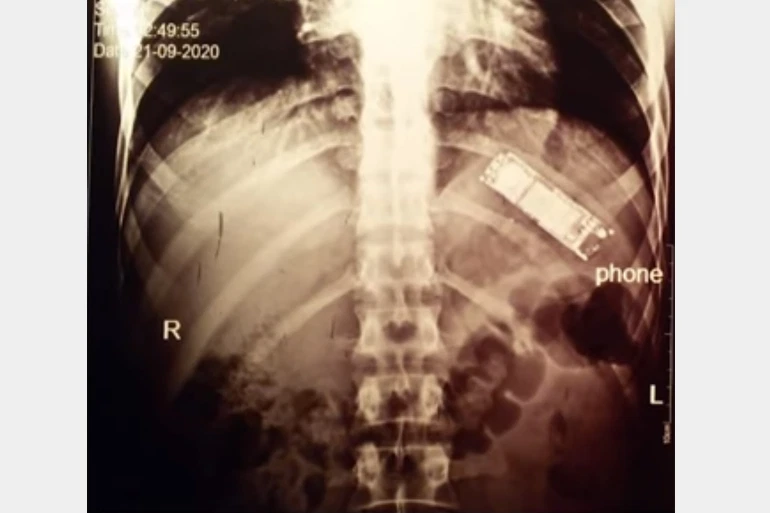

الصومال – افريقيا برس. تداول نشطاء عبر مواقع التواصل الاجتماعي، صورا لفريق طبي، نجح في استخراج هاتف محمول من معدة مريض، في مستشفى بنها الجامعي بمصر.

ولم يتوقع الطبيب أن يجد هاتفا محمولا في معدة المريض، حتى بعد رؤية صور الأشعة، حيث قال “لآخر لحظة كنت بقول (أقول) الأشعة فيها حاجة غلط (شيء خاطئ)، لحد ما طلعناه (حتى أخرجنا الهاتف من معدته)”!